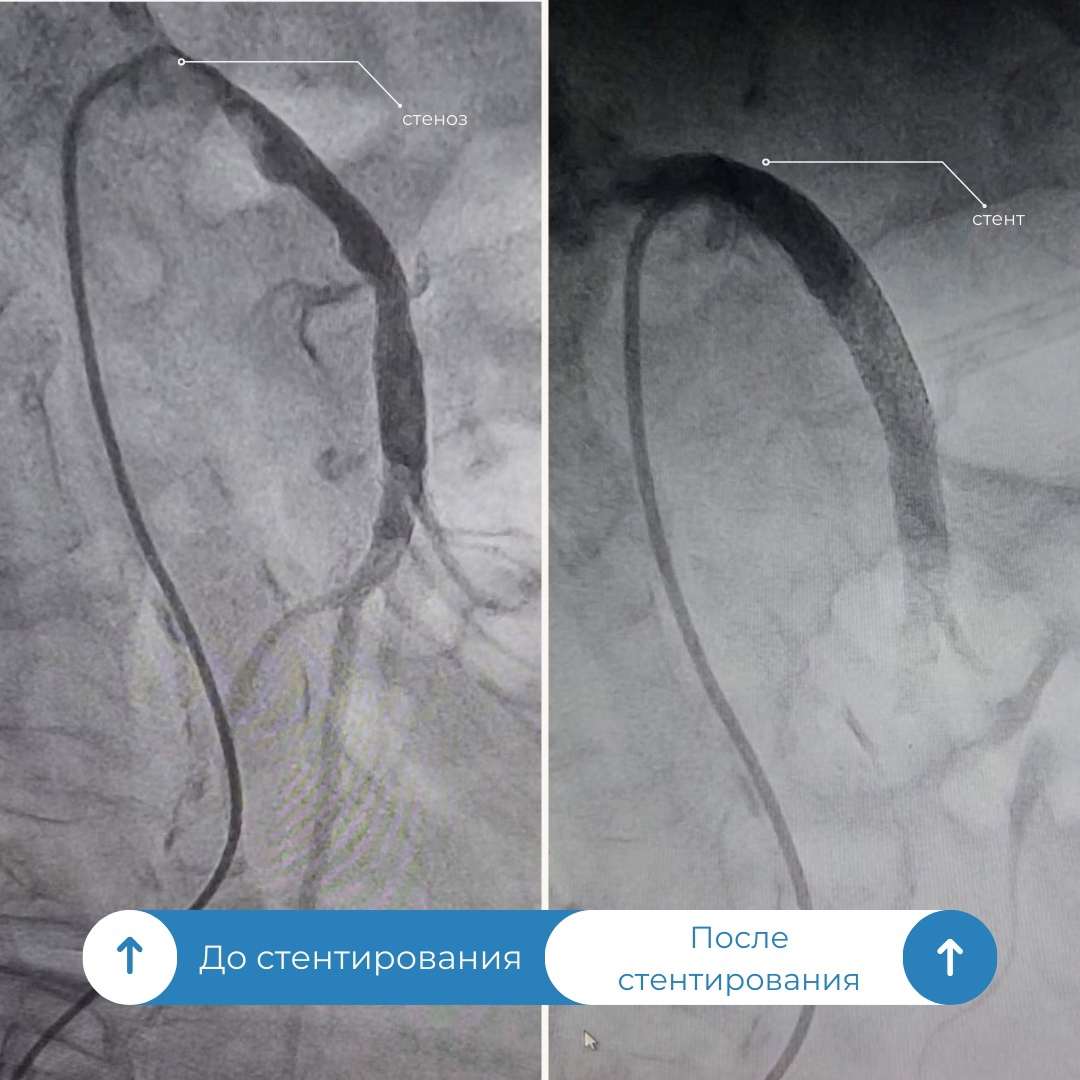

«Усугублялась ситуация и тем, что у пациентки наблюдался выраженный кальциноз, когда соли кальция откладываются на стенках сосудов. Поэтому было решено оценить варианты и возможности развития событий в рентген операционной. Через прокол в бедренной артерии в аорту мы ввели диагностический катетер и установили его в устье верхней брыжеечной артерии, затем ввели контрастное вещество и под рентген-контролем выявили критический стеноз» , – прокомментировал операцию врач по рентгенэндоваскулярному лечению Уйгунжон Жахонгиров.